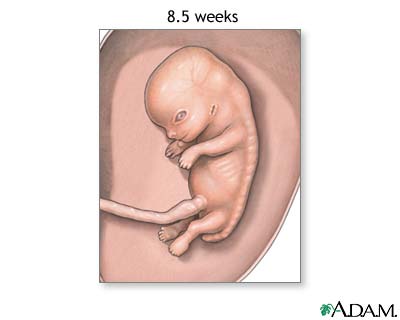

Week 10

- Your baby's eyelids are more developed and begin to close.

- The outer ears begin to take shape.

- Your baby's facial features become more distinct.

- The intestines rotate.

- At the end of the 10th week of pregnancy, your baby is no longer an embryo. It is now a fetus, the stage of development up until birth.

- Fetal heart tones may be detectable by Doppler testing